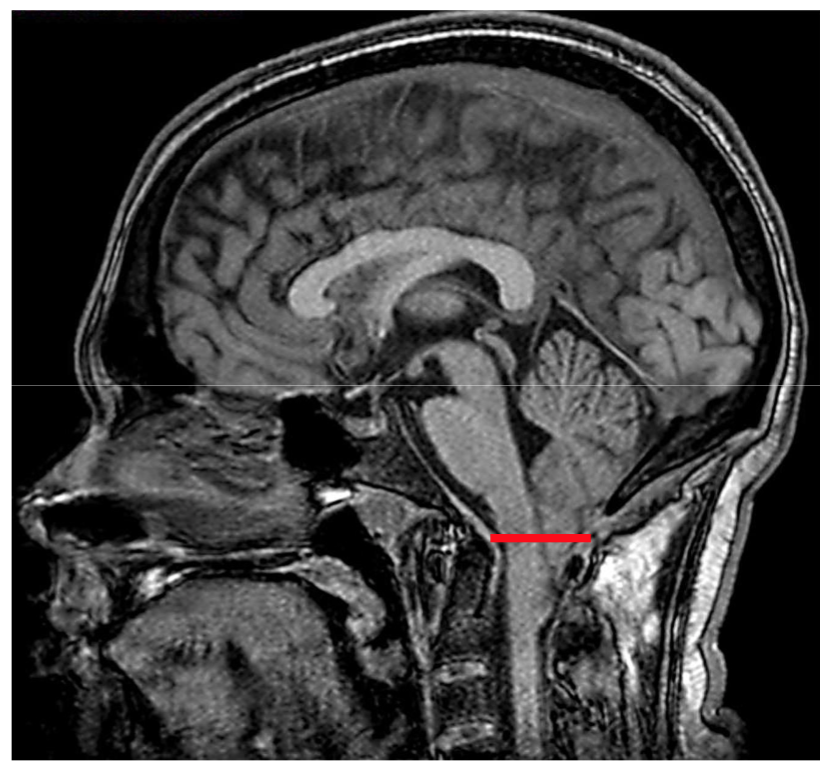

22

Q

You get an MRI like this, what are the two things you are thinking?

A

CSF leak

or

Chiari Type I Malformation

What is Chiari Type I malformation headache & what are the symptoms?

cerebella tonsillar ectopia ~5mm

• Symptoms:

• occiptial/suboccipital headache

• pain triggered by valsalva

• associated with syrngomyelia